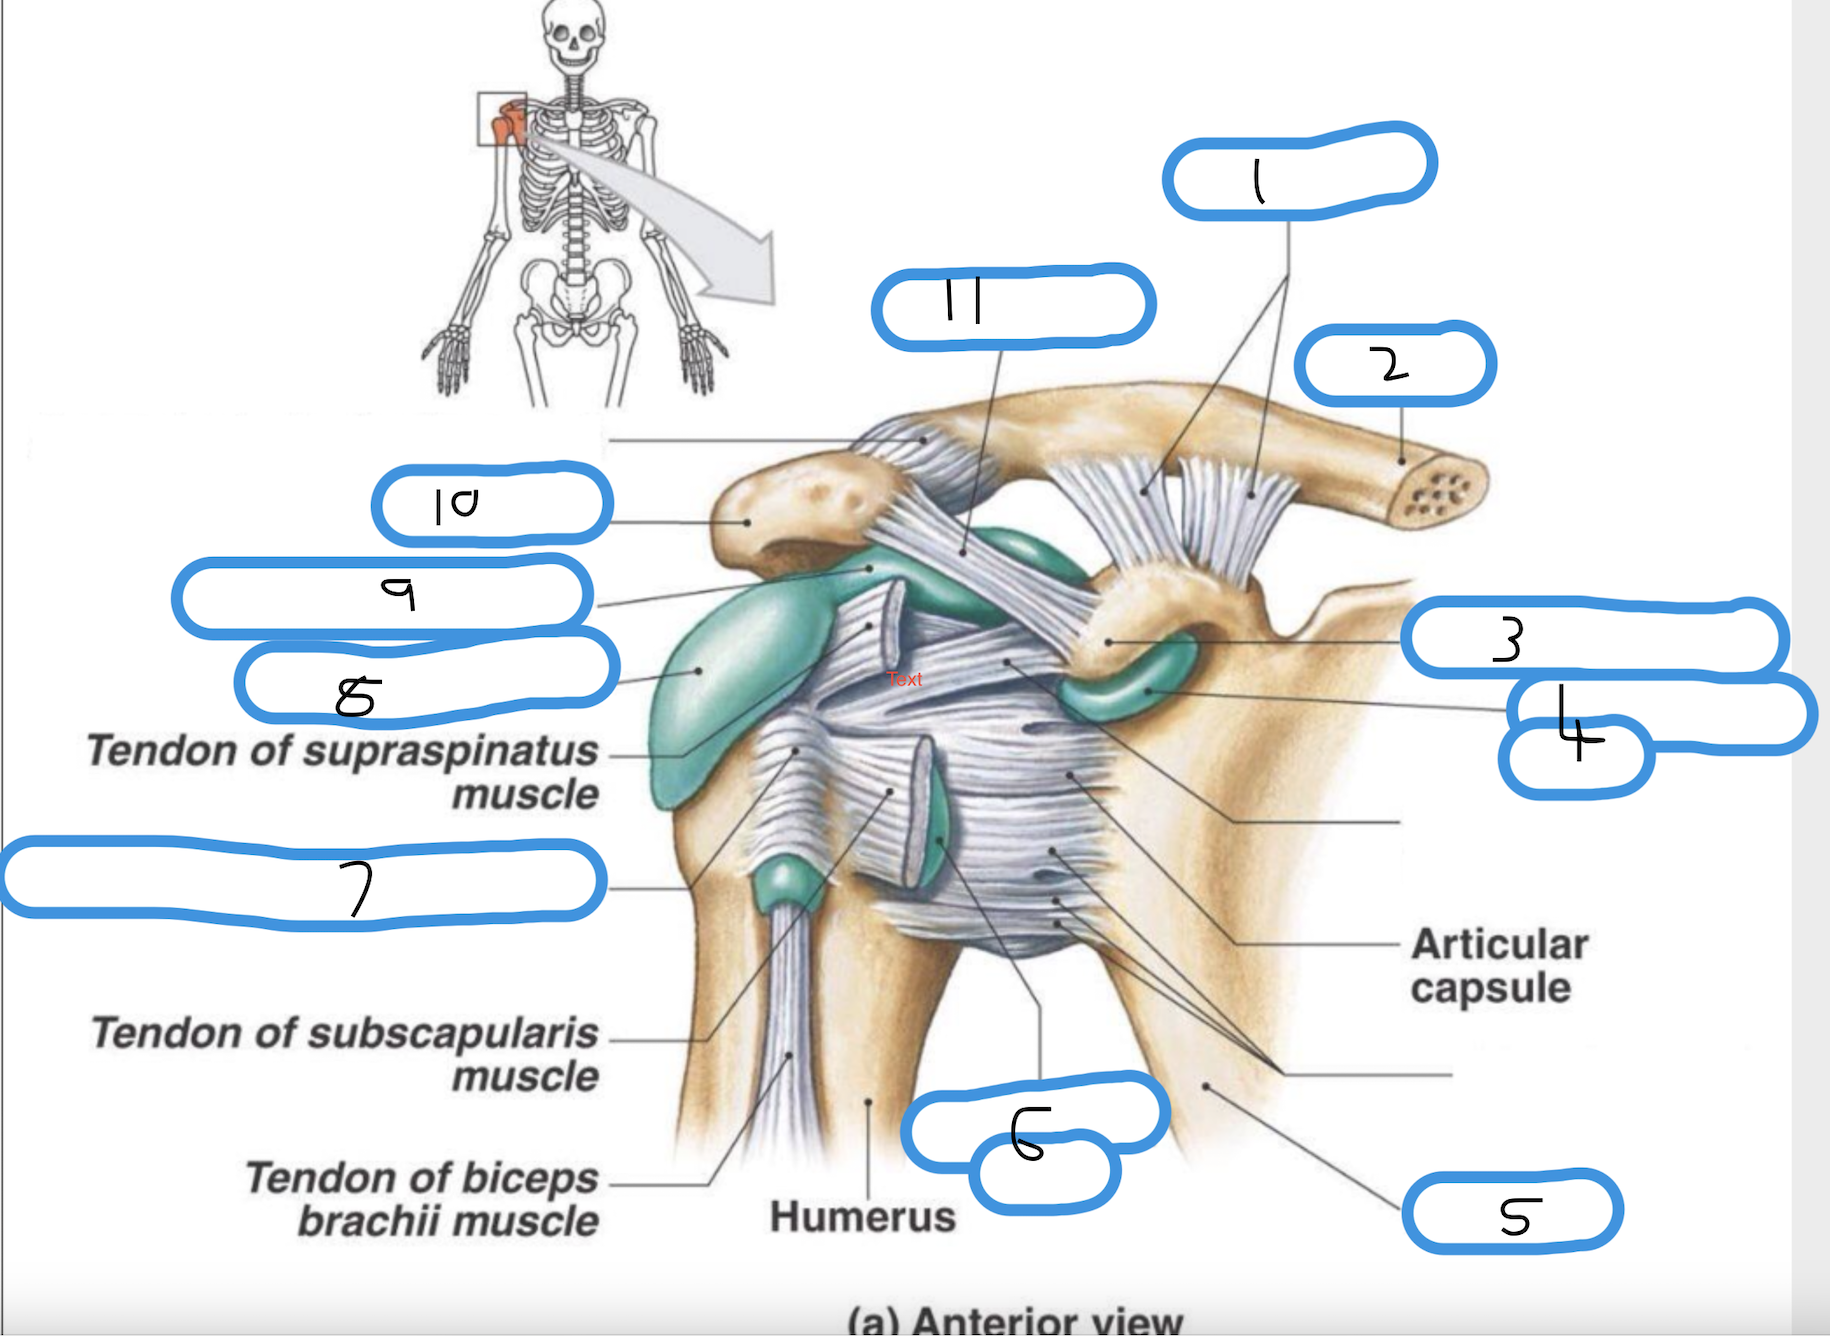

Label diagram from 1-12

coracoclavicular ligament (trapezoid and conoid)

clavicle

coracoid process

sub coracoid bursa

scapula

subscapular bursa

transverse humeral ligament

sub deltoid bursa

sub acromial bursa

acromian process

coracoacromial ligament

deltoid ligament (superior, middle, inferior)